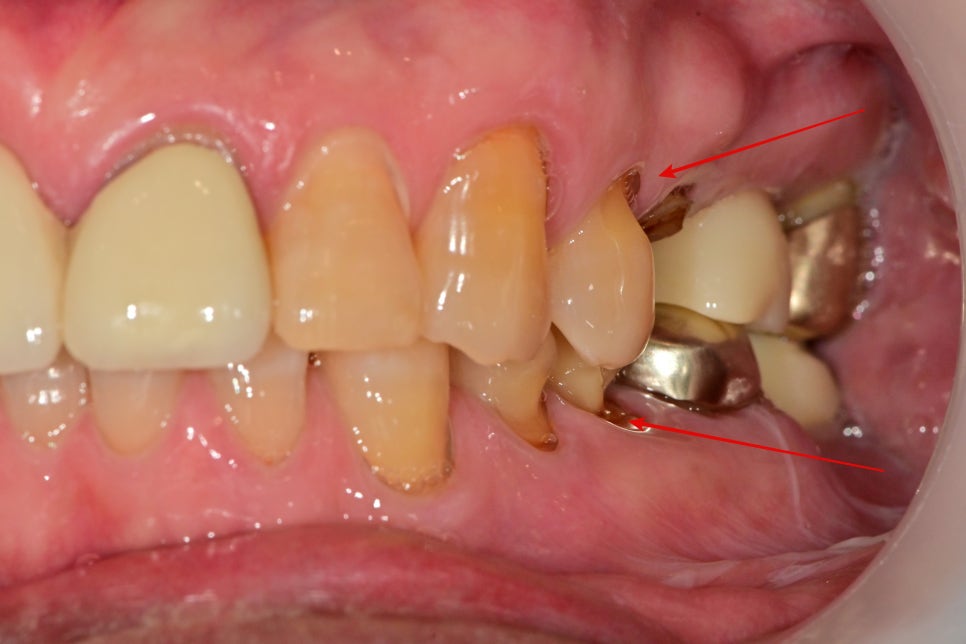

과거에 씌운 치아가 빠졌었고, 치아가 깨져있어요.

왼쪽 위 치아 중 두 번째 작은 어금니의 머리 부분이 파절이 되어있습니다.

과거에 크라운으로 씌워놨지만 검은색으로 보이는 치아의 목부분이 충치가 생기면서 치질이 약해진 상태에서

반복된 과도한 교합력으로 인해 머리 부분이 파절이 된 상태에서 내원해 주셨습니다.

환자분이 과도한 교합력으로 인한 약한 치아 부위가 파절된 것을 어떻게 유추할 수 있을까요?

파절된 치아의 주변 치아들을 보면 짐작할 수 있습니다.

아마 과거에 위, 아래 큰 어금니들은 이미 파절로 인한 크라운치료 또는 발치 및 임플란트 치료가 진행된 상태입니다.

임플란트 보철물이 자연치아보다 큰 저작력을 제공하기 때문에 그에 따라 저작활동을 하며 치아들이 많이 파절, 마모가 되어있는 상태였습니다.

측면에서 관찰된 사진입니다.

치아의 목 부위라고 불리는 치경부의 치아가 많이 깨져 있습니다.

이 또한 과도한 저작력으로 인한 치아 파절로 보입니다.